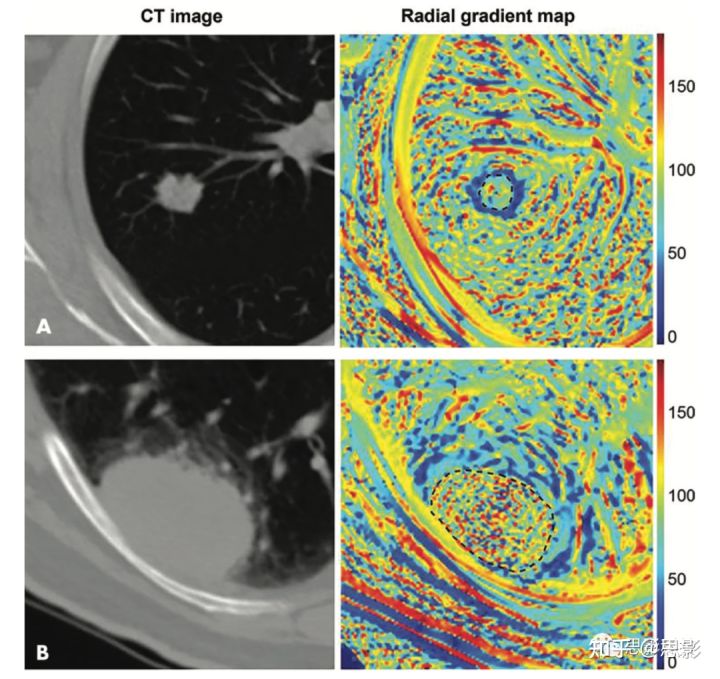

图2,影像组学可以量化肿瘤的视觉特征。

Tunali等人使用两名患者(A和B)肺癌病变的CT图像(左)计算描述肿瘤边缘界面(黑色虚线勾勒出的肿瘤)的径向梯度图(右)。肿瘤周围区域map的简单平均值和标准差的量化与生存率相关,并与肿瘤边缘的定性语义特征相关,如边界定义。

最近一些研究表明,基于影像组学的语义和传统图像特征可能提供有价值潜在的生物学机制,因为它们与视觉表型明显相关。Yip等人量化了非小细胞肺癌中语义特征和影像组学特征之间的相关性。重要的是,作者利用观察到的关系来讨论影像组学特征变化的物理和生物学机制。同样,Tunali等人引入了一个自动化方法,用于量化肿瘤-基质界面特征,显示其与非小细胞肺癌生存率的关系。然后,通过显示与语义评分特征(如分叶和边界定义)的显著相关性来验证对新特征的视觉解释。图2显示了这种定量方法的一个示例。量化肿瘤-基质表皮特征,显示其与非小细胞肺癌生存率的关系。然后,通过显示与语义评分特征(如分叶和边界定义)的显著相关性来验证对新特征的解释。图2显示了这种定量方法的一个示例。在模型中引入决策树也可以简化对特征信息内容的直观理解。